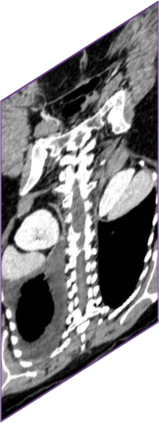

Due to the constraints of the imaging device and high cost in operation time, computer tomography (CT) scans are usually acquired with low intra-slice resolution. Improving the intra-slice resolution is beneficial to the disease diagnosis for both human experts and computer-aided systems. To this end, this paper builds a novel medical slice synthesis to increase the between-slice resolution. Considering that the ground-truth intermediate medical slices are always absent in clinical practice, we introduce the incremental cross-view mutual distillation strategy to accomplish this task in the self-supervised learning manner. Specifically, we model this problem from three different views: slice-wise interpolation from axial view and pixel-wise interpolation from coronal and sagittal views. Under this circumstance, the models learned from different views can distill valuable knowledge to guide the learning processes of each other. We can repeat this process to make the models synthesize intermediate slice data with increasing inter-slice resolution. To demonstrate the effectiveness of the proposed approach, we conduct comprehensive experiments on a large-scale CT dataset. Quantitative and qualitative comparison results show that our method outperforms state-of-the-art algorithms by clear margins.